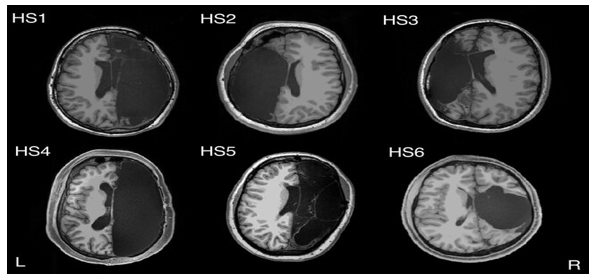

В Калифорнийском технологическом институте провели магнитно-резонансную томографию (сделаны снимки) шестерым пациентам, которым в детстве было удалено полушарие мозга или крупная его часть из-за редкой и страшной формы эпилепсии

Эта процедура называется гемисферэктомией. Сравнение со снимками контрольной группы (6 участников) и с базой данных из 1482 изображений показало, что паттерн активности мозга в состоянии покоя у участников с половиной мозга удивительно похож на наблюдаемый у людей, имеющих весь объем мозгового вещества.

Выявлено и отличие: у пациентов было найдено гораздо больше связей между различными

мозговыми сетями, которые управляют такими вещами, как внимание, сенсорная и лимбическая (эмоции и память) деятельность, и часто вовлекают оба полушария головного мозга, а внутрисетевая активность связана со способностями, такими как моторная деятельность, тогда как соединения между сетями необходимы для разных исполнительных способностей, например рабочей памяти.

Например, сеть внимания показала больше подключений к визуальной сети, чем обычно. Это увеличение связей между сетями отражает то, как оставшаяся часть мозга компенсирует потерю его «вычислительных» ресурсов, чтобы поддерживать когнитивные функции и сознание.

У этих 6 пациентов американские нейрофизиологи провели первые детальные замеры такого рода, чье полушарие удалили в первые месяцы или годы их жизни. Поместив их в магнитно-резонансный томограф, ученые проследили за тем, как менялся рисунок активности в четырех сотнях участков их коры и глубинных слоев мозга, отслеживая изменения в концентрации кислорода в сосудах головы.

Наблюдая за одновременным включением нервных клеток в разных регионах мозга, Климанн и ее коллеги составили карту подобных связей и выяснили, насколько сильно эти области были связаны между собой. Изначально ожидалось, что эти связи будут ослаблены, так как многие из них соединяют области в разных полушариях мозга. В реальности все было наоборот – среднестатистическая сила связей между разными частями мозга их шести подопечных была заметно выше, чем у представителей контрольной группы с двумя полушариями.

Результаты исследования показали, что у людей с одним полушарием мозга специальные сети в мозге, отвечающие за речь, зрение и другие функции, работали так же, как и у здоровых пациентов. В результате сканирования мозга 29-летней женщины было выяснено, что пациентке не хватает некоторых структур в мозге, которые нужны для восприятия запаха.